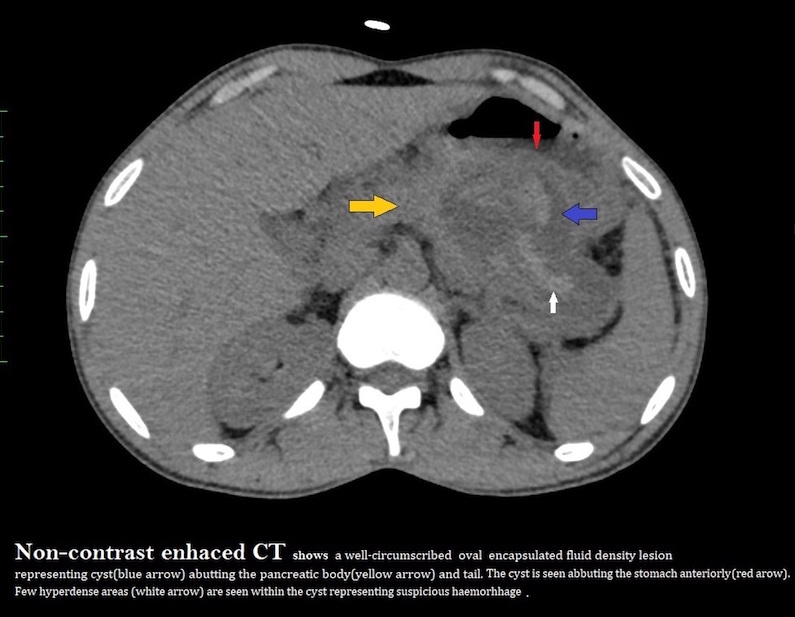

A well-defined oval cyst isseen abutting the pancreatic body and tail, suggestive of a pancreatic pseudocyst. The pancreatic duct is minimally prominent. Thecyst is seen anteriorly abutting the stomach wall with resultant diffuse oedematousthickening of the walls of the stomach.A few ill-defined hyperdensitiesare seen within the cyst, suggestive of chronic hemorrhages/ sludge •Atiny nodular well-defined intensely enhancing lesion is seen along the cyst wall anteriorly on arterialphase representing peseudoaneurysm.

- Pseudocysts appear as well-circumscribed, usually round or oval intra- or peripancreatic fluid collections that are usually surrounded by a well-defined wall. They may or may not have communication with the pancreatic duct.